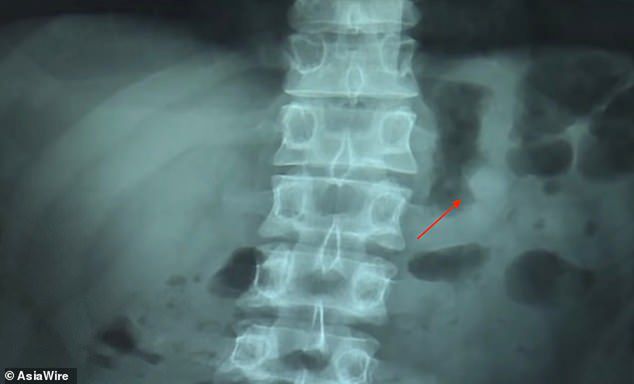

Ben Hsu, bo tak nazywa się mężczyzna, relacjonuje "Daily Mail", że usnął z AirPodami w uszach. Kiedy się obudził, stwierdził brak jednego z nich. – Sprawdziłem pod kocem, rozejrzałem się dookoła, ale nie mogłem go znaleźć – mówi Hsu. – Wtedy zrozumiałem, że dźwięk dochodzi wprost z mojego brzucha – wyjaśnia, jak dokładnie zdiagnozował zaistniały problem.

Pechowiec popędził na izbę przyjęć, gdzie wykonano prześwietlenie. Lekarz potwierdził opinię pacjenta i zalecił środki przeczyszczające, aby pozbyć się ciała obcego.

RTG Bena Hsu / Fot. Asia Wire

Terapia poskutkowała drugiego dnia. Hsu wydalił słuchawkę. Jednak, co zaskakujące, postanowił skorzystać z okazji i wyrazić kilka ciepłych słów na temat firmy Apple i jakości AirPodów. Prawdziwy z niego fan – można by rzec, zwłaszcza mając na uwadze krępujące okoliczności zajścia.

– Słuchawka była nienaruszona, a bateria wciąż miała 41 proc. To było niesamowite – podsumował. Zapewnił też, że teraz jak nigdy jest przekonany o wysokiej jakości produktów Apple'a. I cóż, może coś rzeczywiście jest w kulinarnym powiedzonku, że droga do serca prowadzi przez żołądek ;)